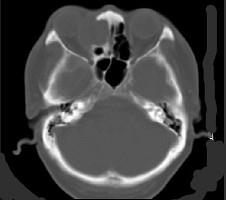

问题 女性,38岁,右侧眼球运动障碍伴眼球突出4个多月,CT扫描如图,请选择正确的描述和答案 ( )

选项 A、考虑为右侧筛窦黏液囊肿 B、考虑为筛窦癌 C、囊性肿块向右侧眼眶内突入,压迫内直肌 D、右侧眶内壁呈受压变薄、断裂 E、右侧筛窦内可见囊性肿块影,边缘光整

答案 ACDE